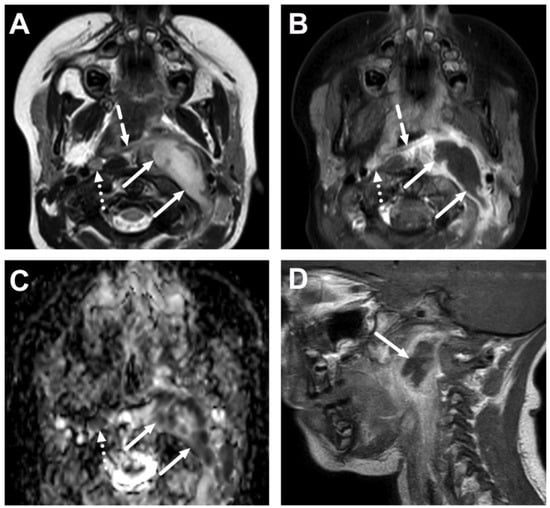

4.3. Oral Cavity

4.4. Sialadenitis